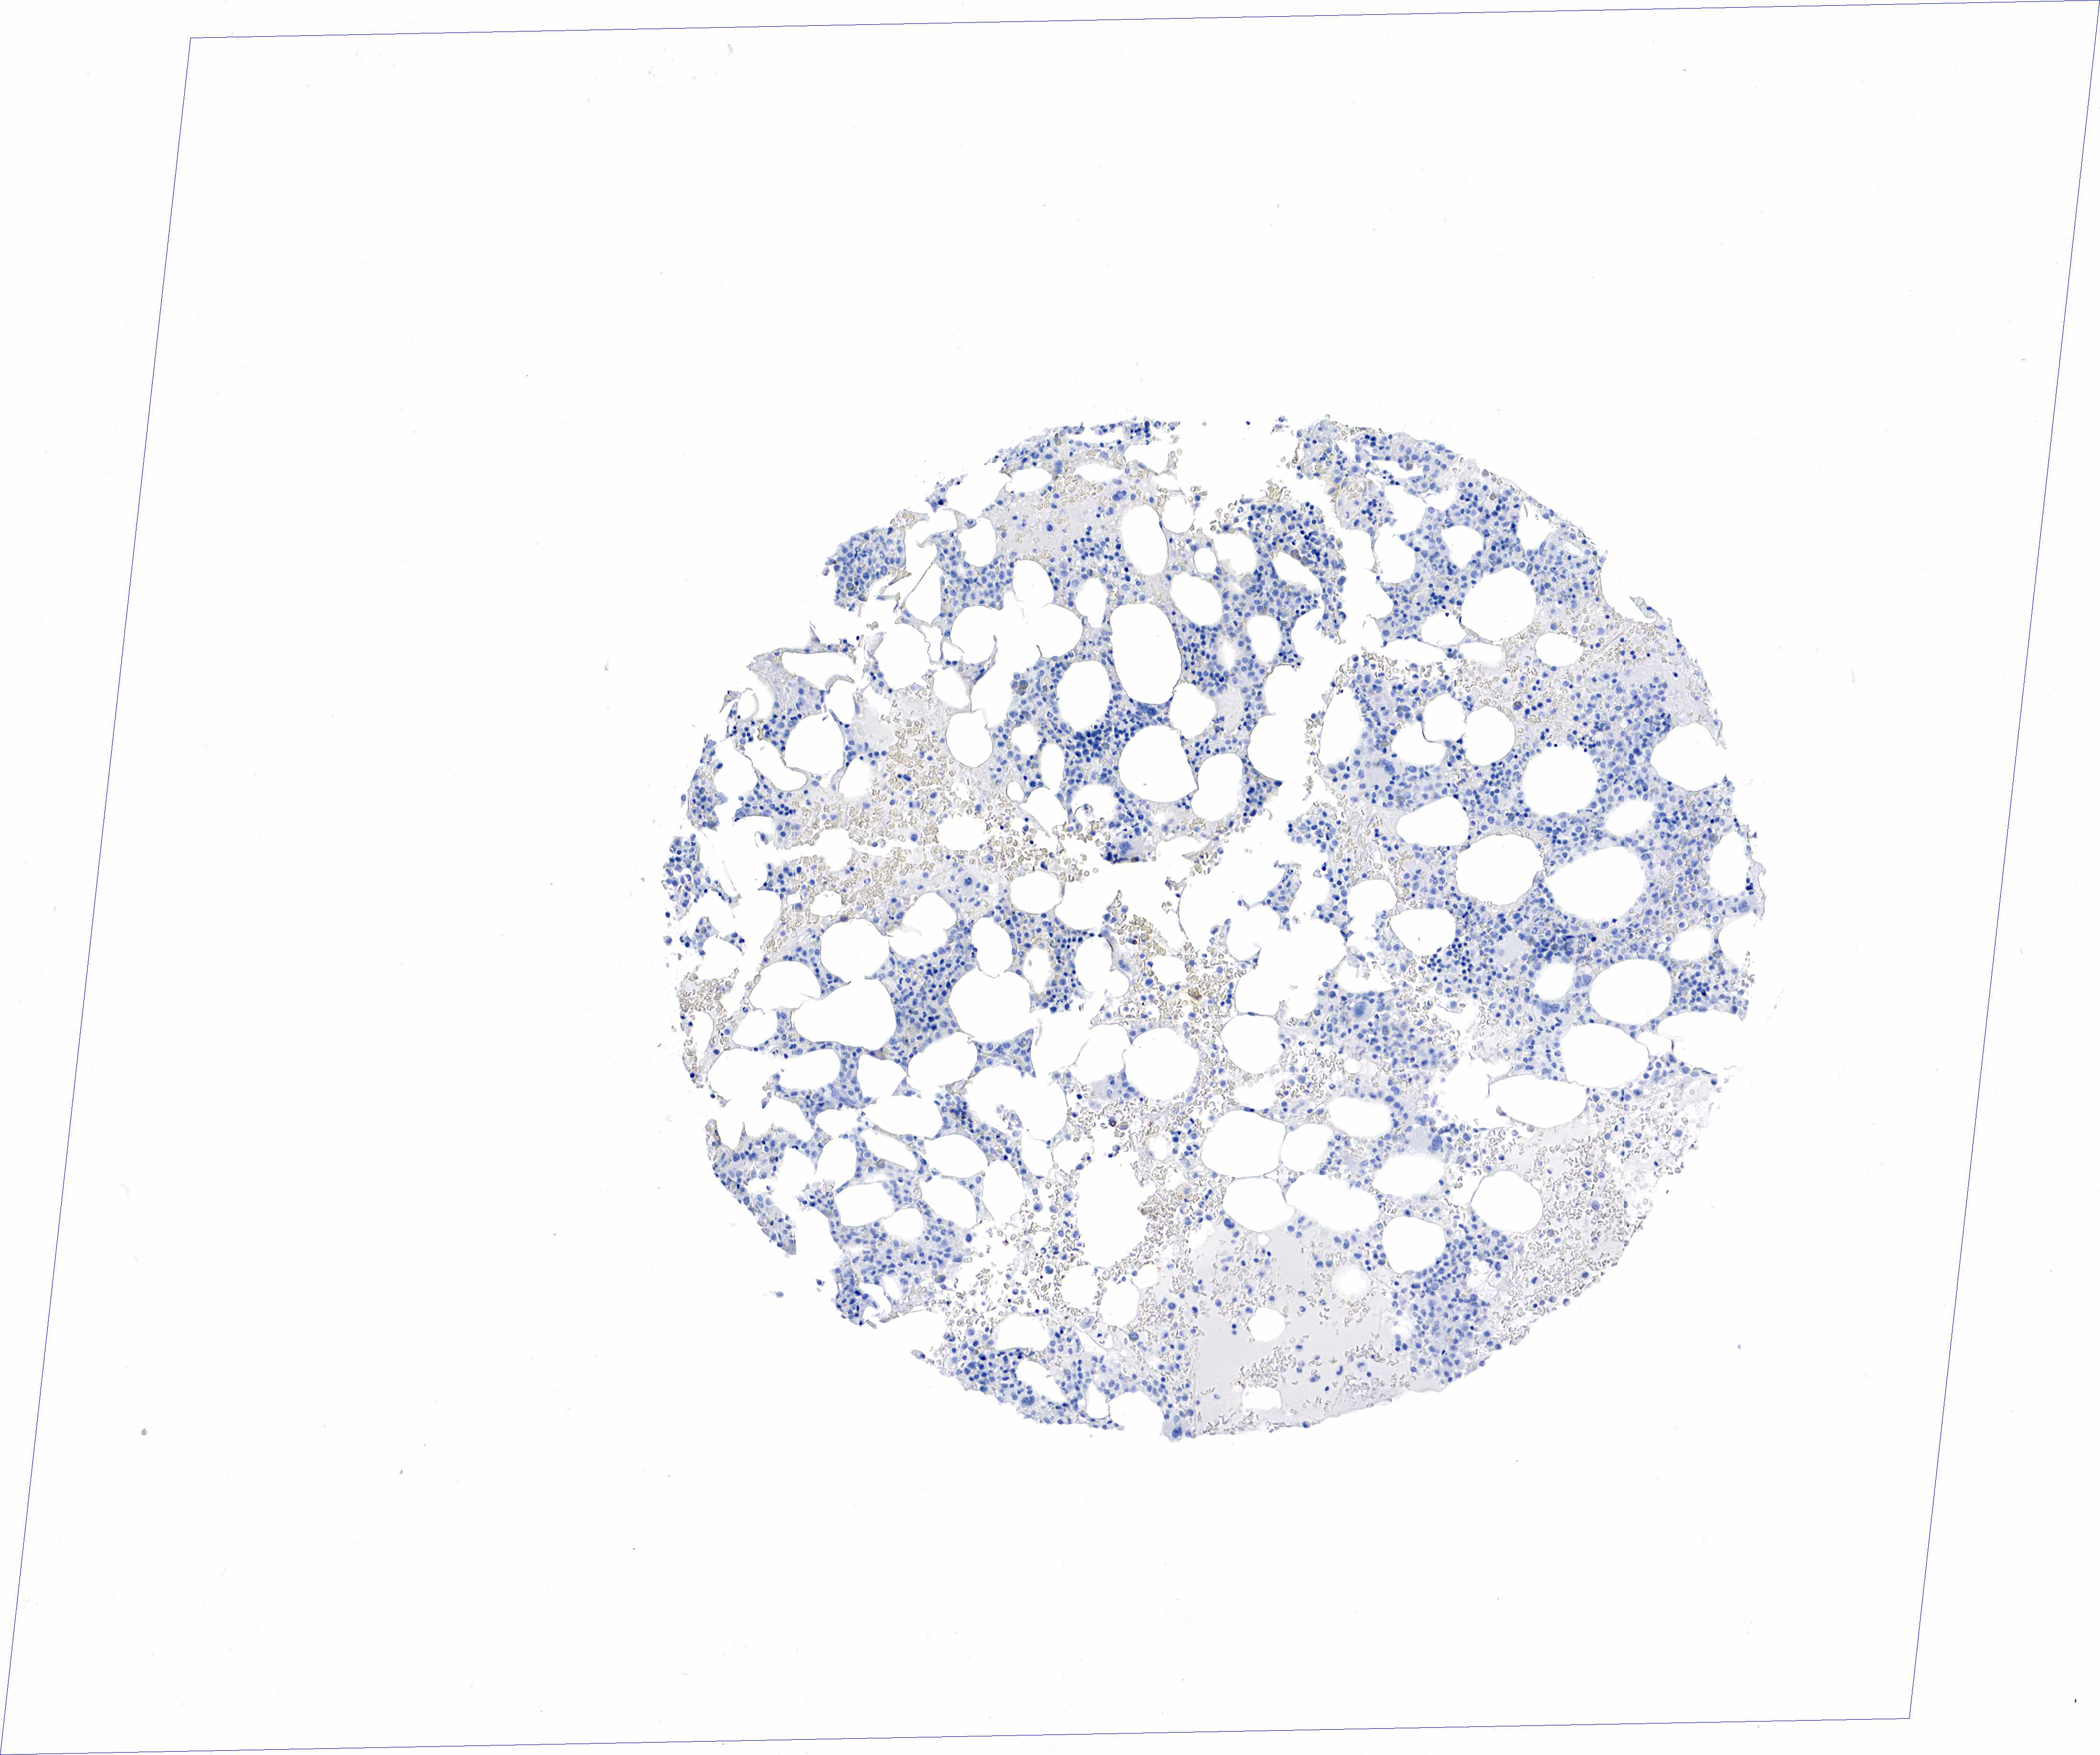

BONE MARROW - HPA RNA-seqi

The RNA-seq details section shows detailed information about the individual samples used for the transcript profiling and results of the RNA-seq analysis.

Information about each individual sample is listed below, including gender, age, a tissue section image and estimated fractions of cell types. nTPM (normalized transcripts per million) values give a quantification of the gene abundance which is comparable between different genes and samples.

Male, age 68

Bone marrow sample 98

nTPM: 0.2

Cell types%

Myelopoietic cells:

50

Erythropoietic cells:

30

Lymphocytes:

10

Monocytes:

5

Blastic cells: